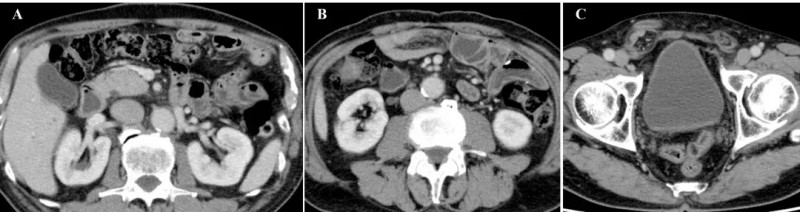

治疗效果十分显著:治疗前腹部CT可见十二指肠周围明显扩张的大网膜(详见下图A箭头所示)、大量恶性腹水(详见下图B、C)。

▲图源“Cureus”,版权归原作者所有,如无意中侵犯了知识产权,请联系我们删除

而在完成第6次治疗后,患者症状大幅改善。最终在第8次治疗后1个月,恶性腹水完全消失,腹胀、腿部水肿消退,食欲恢复,原发病灶与转移性淋巴结持续缩小,腹膜播散的影像学特征已不明显——腹腔内脂肪性粘稠组织大网膜消失(详见下图A),腹水消退(详见下图B),仅右侧腹股沟疝因之前大量腹水导致的腹压仍持续存在(详见下图C)。